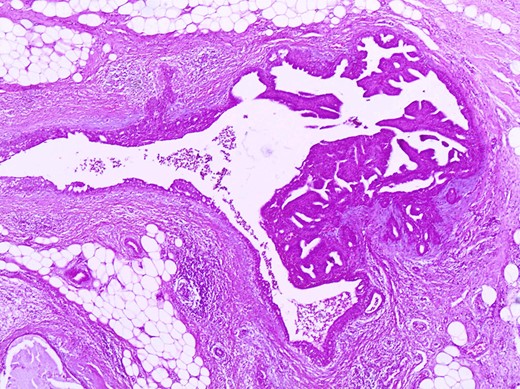

The histologic examination revealed an intraductal papilloma of 9 mm in maximum diameter with no evidence of atypia or malignancy (Figs 3,4 and 5).

Partially dilated duct with papillary projections within its lumen (in the right side of it) (H+Ex400).